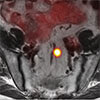

Prostate cancer is one of the most common cancers in men. The new prostate-specific membrane antigen (PSMA) PET imaging will significantly improve how prostate cancer is detected and treated. The FDA approved the drug for positron emission tomography (PET) imaging of PSMA-positive lesions in men with prostate cancer. 68Ga-PSMA-11 is a radioactive imaging agent that binds to prostate cancer cells to help localize prostate cancer cells.

- Radioactive tracer drug (68Ga-PSMA-11) is injected and attaches to PSMA proteins (prostate cancer tumors overexpress this protein).

- The PET scan detects the concentrated PSMA tracer, pinpointing these tumors for more effective treatment.

- More effective in pinpointing and eliminating tumors not only in the prostate but also throughout the pelvis and the body in cases where the tumors have migrated.